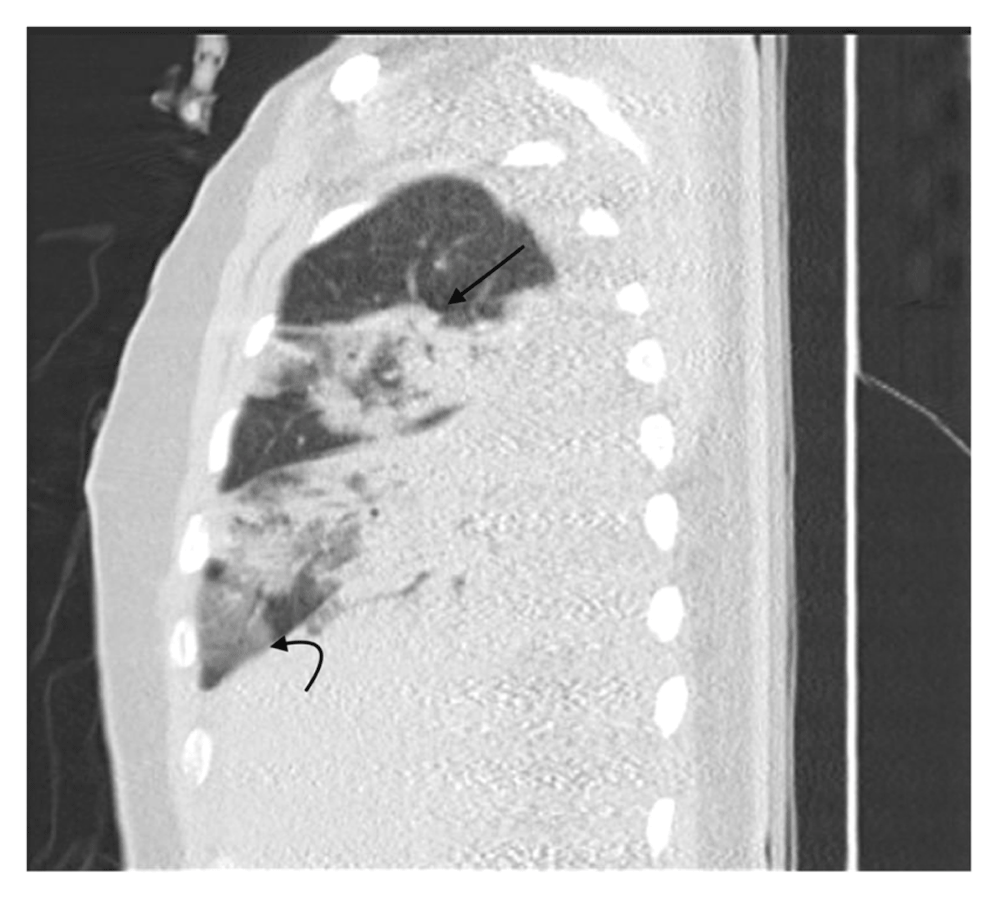

The patient was started on continuous renal replacement therapy (CRRT); his clinical status deteriorated with increased ventilation requirement of FiO2 50% to 80%, PEEP 8 to 16 cm H2O on day 4. A chest X-ray showed multiple bilateral ill-defined patchy opacities in the right lower lung zone (Figure 1). A computed tomography (CT) scan for his chest was done and showed multiple bilateral patchy ground-glass opacities (Figure 2, Figure 3). Bilateral lower lobe consolidations with air bronchogram showed greater involvement of the right lower lobe, while an unenhanced CT of the brain demonstrated hyperdense foci seen in the left inferior frontal, right parietal lobes with surrounding edema, and right central sulcus compatible with intra-parenchymal hemorrhage and subarachnoid hemorrhage, respectively. A follow-up MRI of the brain was obtained, showing an increased gyral pattern of T1 and FLAIR sequence, as observed in the bilateral occipital, bilateral frontal, and right parietal lobes, likely related to laminar necrosis from the anoxic- ischemic event. Gradient recalled echo (GRE) sequence showed scattered areas of blooming artifacts that are likely to be related to recent extensive hemorrhage. The brain findings were suggestive of hemorrhage and hypoxic injuries of vascular causes of previous cardiac arrest events.

The scan shows a right middle lobe central ground-glass density with surrounding consolidation (arrow), giving the appearance of reversed halo sign 'atoll-sign'. A peripheral ground-glass density (curved arrow) is seen in the right lower lobe; a typical picture of coronavirus disease 2019 (COVID-19).